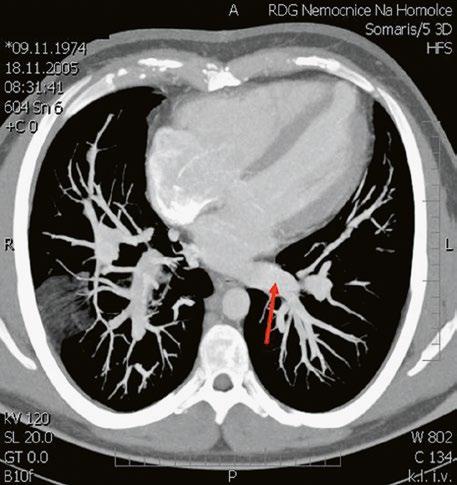

Supravalvární pulmonální stenóza a stenózy větví plicnice bývají součástí komplexních VSV (např. Fallotovy tetralogie) nebo syndromů (Williamsův syndrom, syndrom Noonanové, syndrom vrozené rubeoly, Alagillův syndrom aj.) (Obr. 45.39). Získané stenózy větví plicnice, ale i úplný uzávěr větve plicnice můžeme vidět po spojkových operacích podle BlalockaTaussigové (Obr. 45.40, Obr. 45.41). Pro zobrazení supravalvárních a periferních stenóz plicnice je optimální CT angiografie (Obr. 45.40, Obr. 45.41, Obr. 45.42, Obr. 45.43).

Obr. 45.40 CT angiografie, 8mm stenóza a deformace levé větve plicnice (šipka) po spojkové operaci podle BlalockaTaussigové v dětství LPA – levá větev plicnice, PA – kmen plicnice, RPA – pravá větev plicnice

Obr. 45.42 CT angiografie. Dilatace kmene plicnice (PA), periferní stenóza v oblasti bifurkace a odstupu pravé větve plicnice (RPA) označena šipkou, odstup levé větve plicnice (LPA) je také lehce zúžen.

Obr. 45.41 Uzávěr levé větve plicnice jako následek provedené spojky podle BlalockaTaussigové v dětství, CT angiografie

Obr. 45.43 CT angiografie, šipkou označena významná odstupová stenóza levé větve plicnice (LPA), lehčí stenóza odstupu pravé větve plicnice (RPA), kalcifikace v oblasti pulmonální chlopně